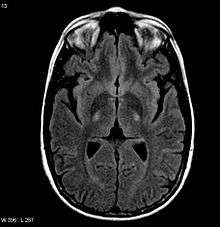

An MRI with increased signal in the posterior part of the internal capsule which can be tracked to the motor cortex consistent with the diagnosis of ALS | |

Because symptoms of ALS can be similar to those of a wide variety of other, more treatable diseases or disorders, appropriate tests must be conducted to exclude the possibility of other conditions.[1] One of these tests is electromyography (EMG), a special recording technique that detects electrical activity in muscles.[1] Certain EMG findings can support the diagnosis of ALS.[1] Another common test measures nerve conduction velocity (NCV).[1] Specific abnormalities in the NCV results may suggest, for example, that the person has a form of peripheral neuropathy (damage to peripheral nerves) or myopathy (muscle disease) rather than ALS. While a magnetic resonance imaging (MRI) is often normal in people with early stage ALS, they can reveal evidence of other problems that may be causing the symptoms, such as a spinal cord tumor, multiple sclerosis, a herniated disk in the neck, syringomyelia, or cervical spondylosis.[1]